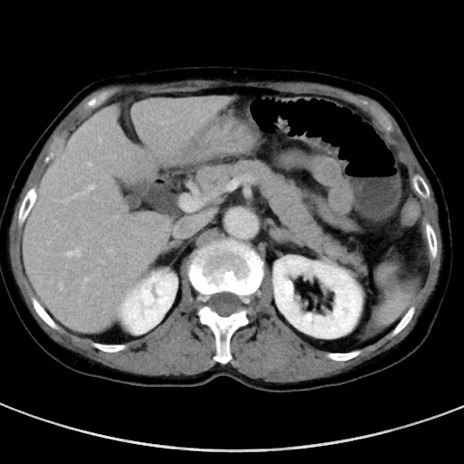

症例23(横断像)

【症例】70歳代女性

【主訴】下腹部痛・嘔吐

【現病歴】2日前より腹痛あり。昨日嘔吐あり。症状改善しないため来院。

【既往歴】胃GISTに対して胃部分切除後。

【身体所見】BT 37.1℃、BP 128/77mmHg、腹部:平坦・軟、下腹部に圧痛あり。

【データ】WBC 10200、CRP 0.31